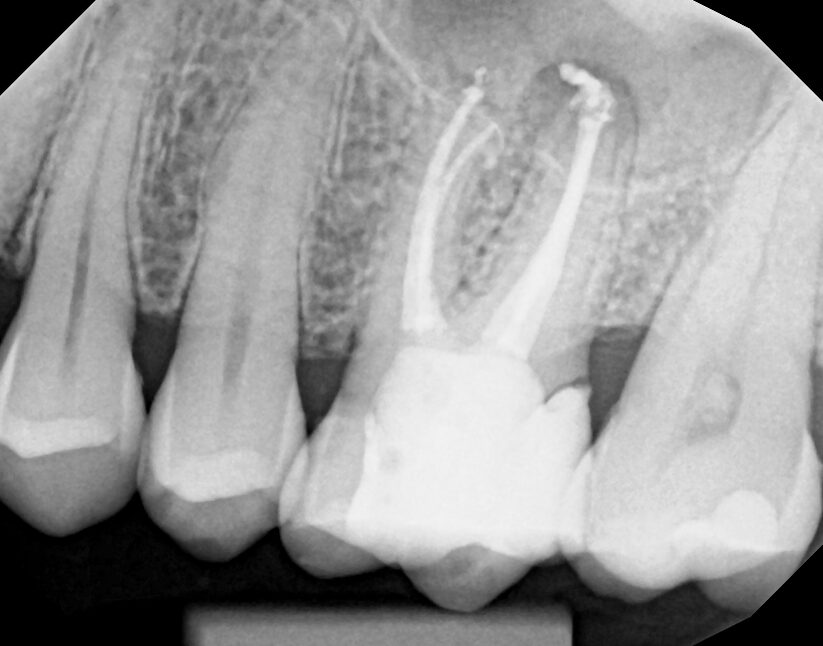

Dive into real-life cases where our products make the difference. From complex retreats to precision instrument retrieval, each case shows how innovation meets clinical success.